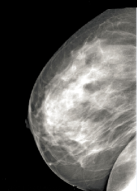

The dataset was mainly collected from St.Gebriel Hospital, Grum Hospital, Betezatha Hospital, Korean Hospital, Kadisco Hospital and Pioneer Diagnostic. The MG images were collected with their document reports that show the screening and diagnosis results of the patients. The documents report results were based on the pathology confirmation and Breast Imaging-Reporting and Data System (BI-RADS). More than 5000 x-ray mammogram images that were diagnosed between 2016 and 2018 as shown in table 1 were collected and some of the samples are shown in figure 1. This work considered only the mass abnormality from the collected MG images, that is 1588 full mammogram images which have mass abnormality and annotated by professional radiologists using the labelMe Russell et al. (2008) annotation tool. The dataset was divided into training (80%), validation (10%), and testing (10%).

Refer to caption

(a)

(b)

(c)

Figure 1: Sample of MG images during acquisition stage. The mammogram images are from different mammography x-ray sources: (a) from Girum Hospital, (b) from Pioneer Diagnostic Center, and (c) from St. Gebriel Hopital.